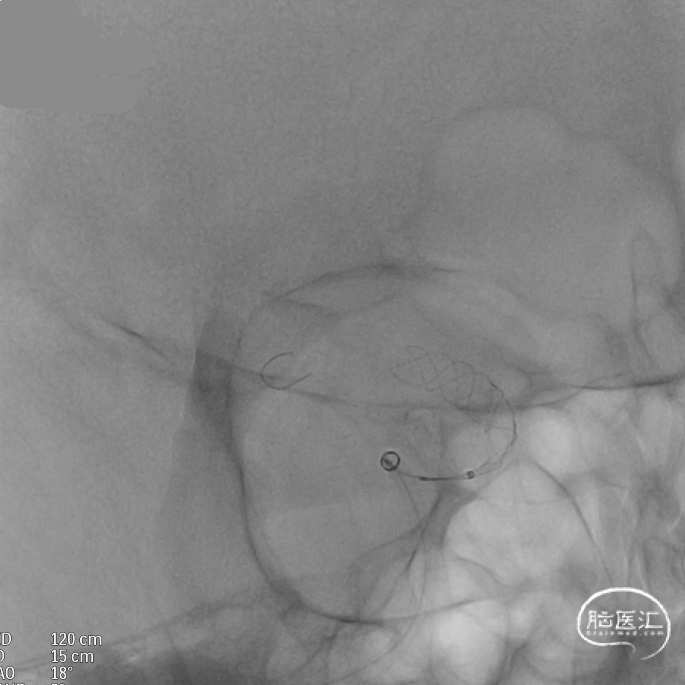

支架到位,原位释放,前段打开。

造影确认支架远端打开充分,贴壁良好,继续推送支架。

支架全部释放,调整张力,微导管通过支架,回收输送导丝。

支架内使用成襻微导丝进行按摩,使支架充分贴壁。

术后造影:支架充分覆盖动脉瘤瘤颈,贴壁良好,瘤体内可见造影剂滞留。

术后支架显影:定位精准,未覆盖颞前动脉及大脑前动脉。